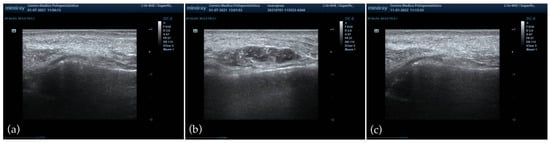

HFUS was performed in all patients at baseline, immediately after injection, and at 1, 3, and 6 months of follow-up. At baseline, imaging confirmed the absence of residual permanent or biodegradable fillers in the NLF area, thereby ensuring adherence to the exclusion criteria, and no abnormalities were detected in soft tissues or vascular structures. Immediately post-injection, ultrasound documented a homogeneous distribution of the filler in the deep anatomical plane, without evidence of vascular compromise or superficial misplacement. Subsequent evaluations at 1 and 3 months confirmed the persistence of correct filler positioning, showing progressive integration into the surrounding tissues and the absence of nodules, granulomas, or inflammatory infiltrates [Figure 5]. At the final six-month assessment, ultrasound confirmed the continued absence of late-onset inflammatory reactions or foreign body responses, and the filler appeared well integrated, with preserved homogeneity and no abnormal findings.

Figure 5. HFUS evaluation of the NLF. (a) Baseline imaging showing absence of pre-existing filler material and normal soft tissue architecture; (b) immediate post-injection assessment demonstrating homogeneous distribution of the PEGDE-crosslinked HA filler in the deep anatomical plane, without vascular compromise or superficial misplacement; (c) six-month follow-up confirming progressive tissue integration, preserved homogeneity, and absence of nodules, granulomas, or late-onset inflammatory reactions.

Similarly, HFUS confirmed correct anatomical placement, homogeneous filler distribution, and progressive tissue integration, with no evidence of nodules, granulomas, or late-onset inflammatory changes during the six-month follow-up. These results corroborate prior studies demonstrating the utility of ultrasound in monitoring filler positioning, identifying vascular compromise, and differentiating benign nodules from inflammatory complications [33,34,35,46]. The absence of abnormal findings in our study strengthens the evidence of safety and biointegration. These findings are consistent with recent evidence showing that HA-based injectable formulations enriched with amino acids demonstrate good local biocompatibility and predictable soft-tissue integration, as reported in mesotherapy and neck rejuvenation protocols [47,48]. Such studies underscore the relevance of combining clinical evaluation with instrumental and imaging techniques to objectively assess tissue response and treatment safety.